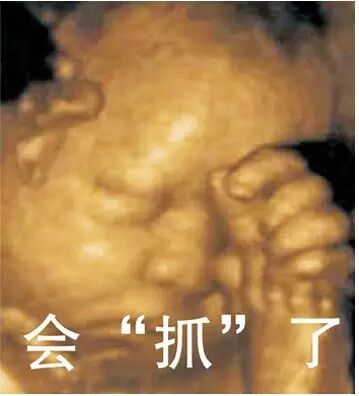

下面,我们来了解六个月胎儿四维彩超图

四维彩超大的优点是检测筛查胎儿畸形,为早期诊断胎儿先天性体表畸形和先天性心脏提供治疗。同其他超声诊断过程相比,四维彩超还能对胎儿的表体进行检测,筛查胎儿畸形:如唇裂,脊柱裂,大脑、肾、心脏、骨髓发育不良等,以便尽早的进行治疗。另外,四维彩超还有另一个功能,那就是可以给腹中的宝宝拍写真像片。

建议孕妇在以下孕期内进行检查比较好,四维彩超的佳时间是孕期22--26周(也就是怀孕5-6个月)。因为这是正是胎儿大脑突飞猛进的发育时期,此时的胎儿机构已经形成,胎儿大小及羊水也适中,在宫内的活动空间较大,胎儿骨骼回声影响较小,图像也比较清晰。所以六个月胎儿是可以做四维彩超的,而且这时也是做四维彩超的佳时间。